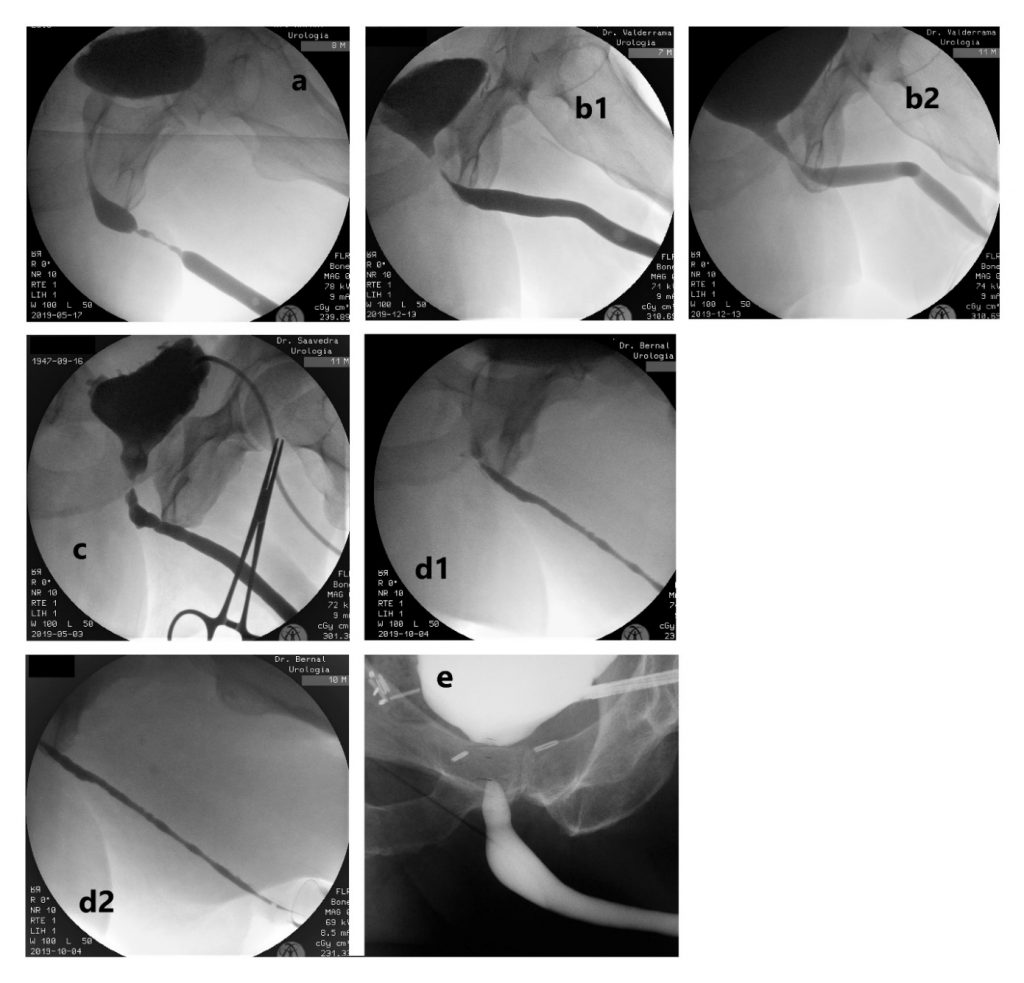

- La uretrocistografía retrógrada/miccional (UCG), es un examen dinámico que se realiza mediante la instilación uretral de contraste hidrosoluble bajo fluoroscopía y se recomienda que siempre sea hecha por el urólogo entrenado.20 Es el examen de elección para etapificación de las E/E. La UCG se encarga de definir la longitud, ubicación, severidad y número de las E/E. Además, da información sobre fístulas, duplicación uretral, falsa vía y el status del cuello vesical. El estudio completo consta de 2 fases: la fase retrógrada dibuja la uretra anterior y la fase miccional dibuja la uretra posterior, no siendo intercambiables, como se muestra en las imágenes.

La fase retrógrada debe realizarse con el paciente en decúbito lateral con inclinación de 45°, permitiendo ver un orificio obturador “ocluido” en la imagen; con la cadera inferior flectada igualmente en 45° y la cadera superior extendida, y con el pene en estiramiento. (Figura 5).

La fase miccional debe hacerse con la mesa en posición vertical y el paciente con deseo miccional, haciendo el registro en forma continua. (Figura 6).

En general, el gold standard en términos de éxito, es la EPA, sin embargo, hay variadas situaciones en que los efectos colaterales la hacen poco aconsejable. Dentro de las técnicas de aumento, la evidencia favorece a los injertos de mucosa oral por sobre los colgajos de prepucio, por el mayor riesgo de complicaciones de éstos últimos, a pesar de tener similares tasas de eficacia. Para decidir la mejor técnica se consideran los siguientes factores: ubicación, longitud, grado de obliteración, etiología, continencia y cirugías previas. (Figura 7)

Uretra bulbar: La EPA es altamente recomendada en casos de E/E <2.0 cms como cirugía primaria o en recurrencias, alcanzando más de un 90% de éxito. (Figura 12). Es la primera opción en etiologías traumáticas, permitiendo remover la espongiofibrosis. La técnica de anastomosis no-transectante (non-transecting) es útil en segmentos obliterados de uretra bulbar proximal y media, <2.0 cms, de origen no traumático y con espongiofibrosis leve. En casos de 2-4 cms es planteable la EPA para uretra bulbar proximal, mientras que se prefieren las técnicas de aumento para la bulbar distal. Dentro de estas últimas, las técnicas dorsales son las preferidas para la bulbar en general (onlay o inlay dorsales), aunque además se pueden utilizar onlay ventrales en la bulbar proximal (88% éxito).28 (Figura 13). En casos de segmentos obliterados largos, se puede hacer una EPA ampliada con injerto, para lograr una anastomosis sin tensión. La uretrostomía perineal es una excelente alternativa para pacientes con E/E de uretra anterior recalcitrantes o en pacientes añosos, con uretra posterior sana, detrusor normocontráctil y continencia conservada. (Figura 14).